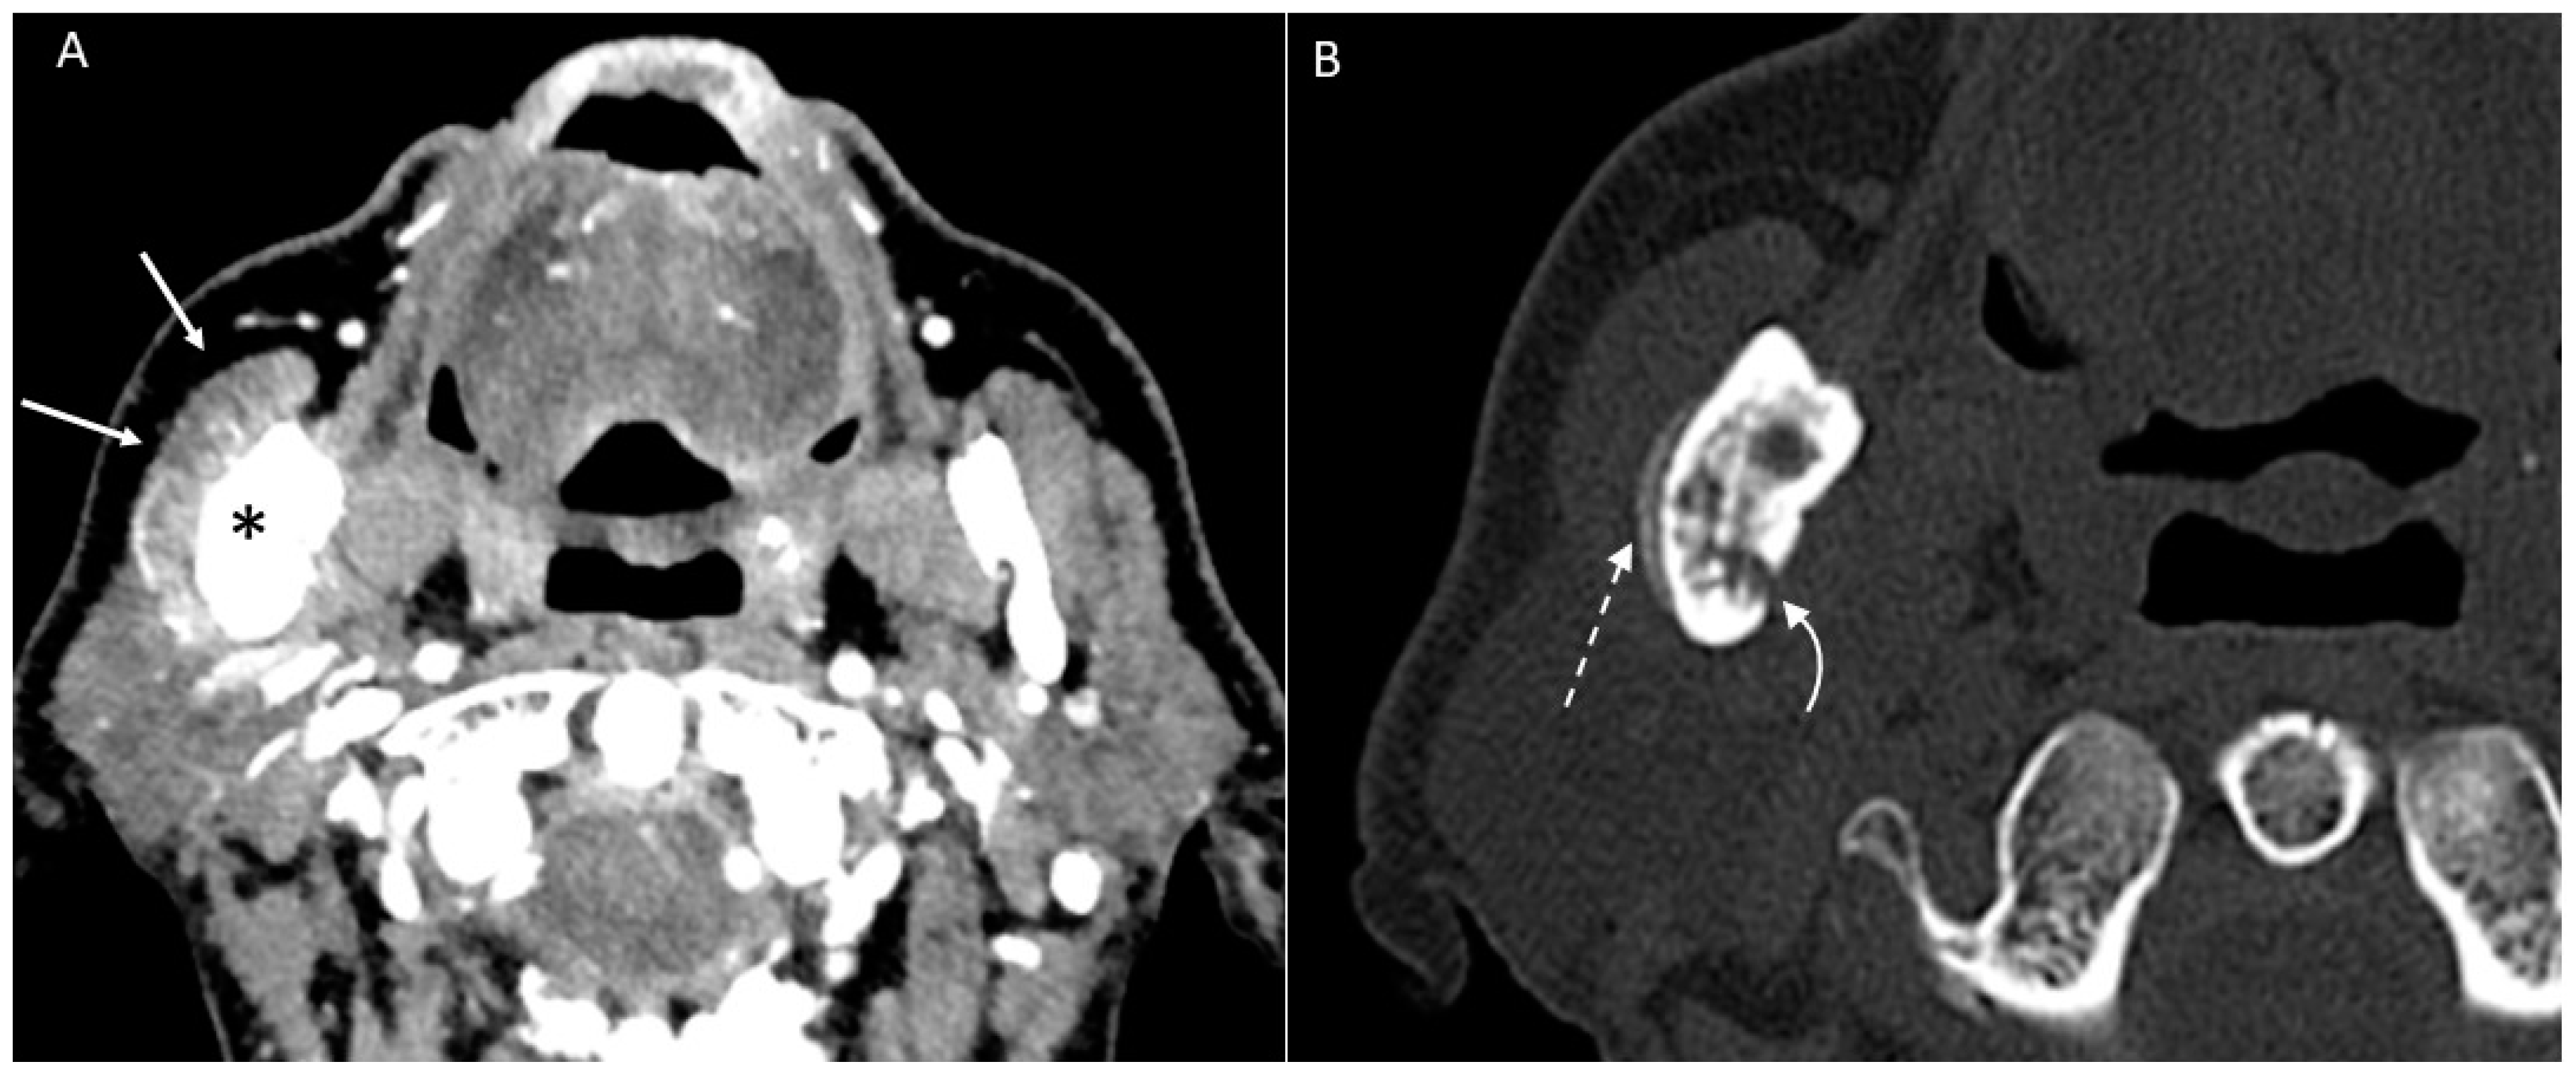

- Puffed cheek technique. The vestibule of the mouth is a virtual cavity due to the contact between the mucosa of the lip, cheek, and gingiva. Puffed cheek technique helps to determine if the lesion is arising from the buccal, gingival, or lingual mucosal surface since patients blow uniformly through pursed lips and the mucosal surfaces appear separated from each other. Therefore, the vestibular cavity can be appreciated as an air-filled horse-shoe-shaped space both on MSCT and MRI (Figure 10 and Figure 11).